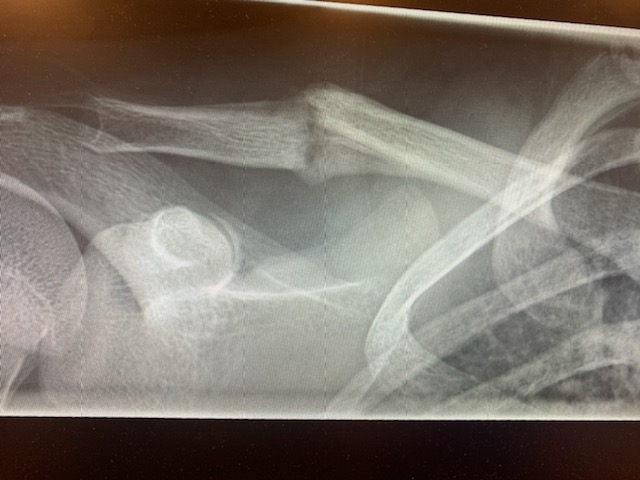

Linnéa tränar med Malmö Dam onsdagen den 27/11 och känner under träning att inte allt står rätt till i axeln.. Det visar sig att hon har ont på samma ställe som hon bröt nyckelbenet på för 8 veckor sedan. Fredrik och hon kör direkt till akuten och det visar sig vara en spricka i samma ben så nu väntar rehab igen. Ev en runda till Stockholm igen och behandling som vi gjorde sist. Vi får se hur det går, men tycker så himla synd om vår stora tös att behöva stå ut med detta. Vi håller tummarna för att hon är tillbaka snart igen. 🙏♥️😔